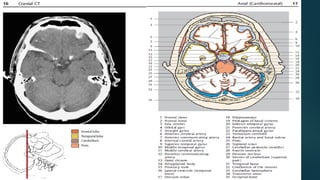

Este documento es el programa para un taller de imágenes del curso de emergencia 2015 impartido por el Dr. Víctor Delgado. El taller se centra en el uso de imágenes médicas para el diagnóstico y tratamiento de pacientes en coma traumático según la base de datos de Marshall. El Dr. Delgado es el único instructor repetido a lo largo del documento.